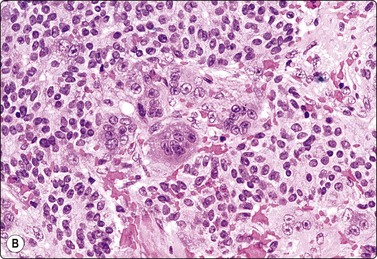

image image

Fig. 7.1 Radiation-induced atypia

(A) The epithelial cells in this irregular cluster show considerable nuclear enlargement, pleomorphism and hyperchromasia, but also some degenerative changes such as loss of nuclear structure (MGG, HP); (B) Corresponding tissue section (H&E, IP).